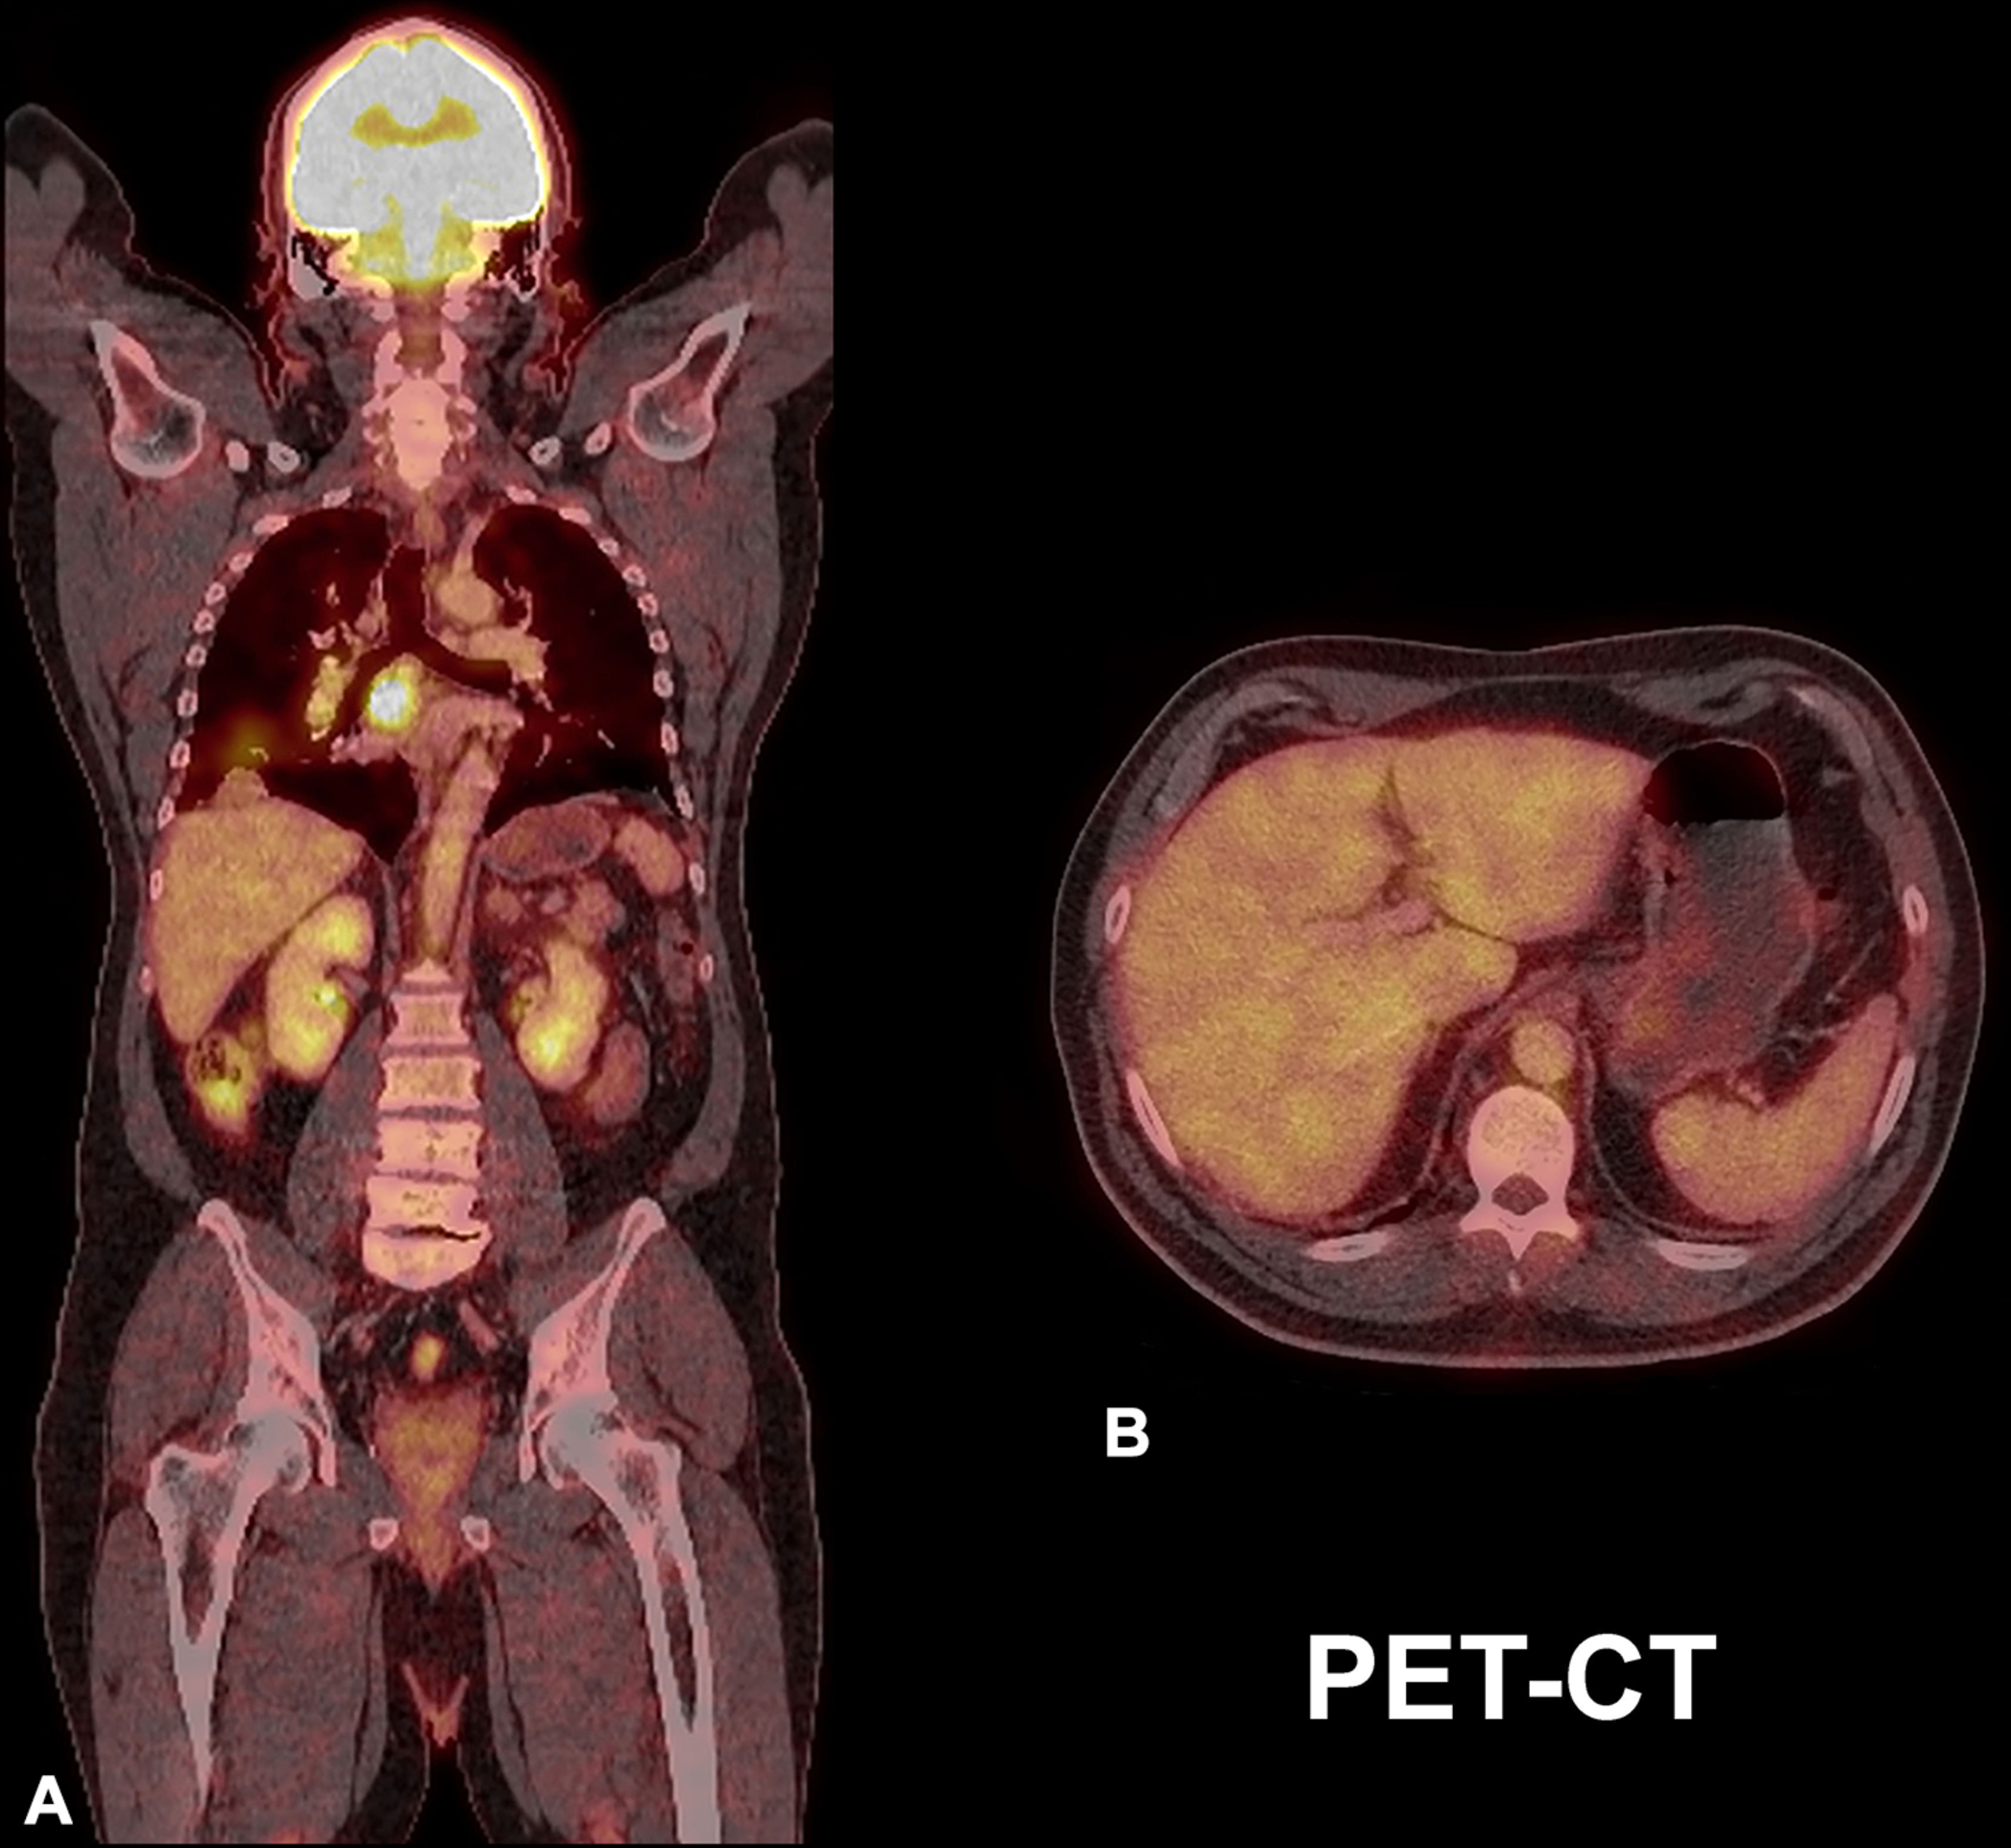

The usefulness of other imaging modalities in HS, such as computed tomography (CT), PET-CT (positron emission tomography-CT), optical coherence tomography (OCT), or confocal microscopy (CFM), is uncertain because, to date, there are no specific reports about their clinical use in HS. CT provides a lower definition for superficial layers in comparison with MRI and ultrasound; therefore, its use is not recommended for diagnosing or monitoring HS. However, abdominal CTs can be helpful in cases with concomitant inflammatory bowel diseases. In the case of Crohn’s disease or ulcerative colitis, CT may help assess the degree of bowel inflammation and rule out the presence of communicating fistulas between the abdominal cavity and wall.

Regarding PET-CT, care must be taken in the interpretation of the inflammatory signs in HS patients with a concomitant history of cancer because they can be mistaken for malignant infiltration ( Fig. 6.2 ).

PET is a nuclear imaging technique that is commonly fused with CT. The fusion of techniques is called PET-CT and allows the detection of anatomical and metabolic functional abnormalities. PET and PET-CT need an intravenous contrast called FDG (F-18 Fluorodeoxyglucose) which distinguishes the hypermetabolism of malignant and inflammatory conditions, named “hot spots.”